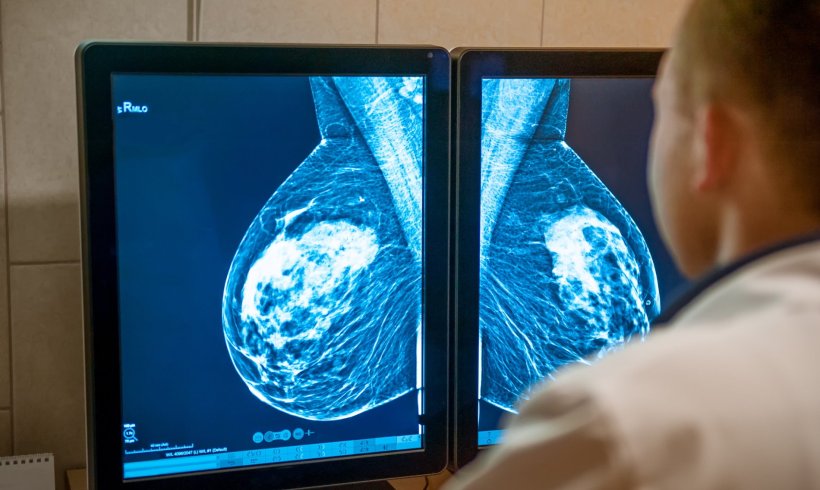

Un team di ricercatori danesi e olandesi ha combinato uno strumento diagnostico basato sull’intelligenza artificiale con un modello di struttura mammografica per migliorare la valutazione del rischio di cancro al seno a breve e lungo termine. Questo nuovo approccio rappresenta un significativo passo avanti nel perfezionamento della capacità di prevedere la complessità del rischio di cancro al seno.

L’intelligenza artificiale (AI) può essere utilizzata “allo scopo di diagnosticare precocemente il cancro al seno rilevando automaticamente i tumori al seno nelle mammografie e misurando il rischio di futuro cancro al seno”, ha affermato il dott. Andreas D. Lauritzen, PhD, del Dipartimento di informatica dell’Università di Washington. l’Università di Copenaghen in Danimarca. Il suo team ha collaborato con ricercatori del Dipartimento di Radiologia e Medicina Nucleare dell’Università Radboud di Nijmegen, nei Paesi Bassi, su un progetto volto a combinare due tipi di strumenti di intelligenza artificiale per sfruttare i rispettivi punti di forza di entrambi gli approcci: modelli diagnostici per stimare il seno a breve termine rischio di cancro e modelli AI della struttura mammografica per identificare la densità del seno, un indicatore importante per valutare il rischio a lungo termine.

Il team di sette ricercatori provenienti da Danimarca e Paesi Bassi ha cercato di identificare se uno strumento diagnostico di intelligenza artificiale disponibile in commercio e un modello di texture di intelligenza artificiale, addestrati separatamente e poi successivamente combinati, potrebbero migliorare la valutazione del rischio di cancro al seno. Hanno utilizzato il sistema diagnostico AI Transpara, versione 1.7.0, della società Screenpoint Medical BV con sede a Nijmegen, e il modello di texture costituito dal codificatore di deep learning SE-ResNet 18, versione 1.0, sviluppato da loro stessi. “Per addestrare i modelli di deep learning è stato utilizzato un set di formazione olandese di oltre 39.245 esami”, ha affermato il secondo autore dello studio, il dottor My C. von Euler-Chelpin, professore associato presso il Centro di epidemiologia e screening, Istituto di sanità pubblica , Università di Copenaghen. I modelli di rischio a breve e lungo termine sono stati combinati utilizzando una rete neurale a tre strati. Il modello combinato di intelligenza artificiale è stato testato su un gruppo di studio di oltre 119.650 donne incluse in un programma di screening del cancro al seno nella regione della capitale danese per un periodo di tre anni da novembre 2012 a dicembre 2015, con almeno cinque anni di follow-up. dati. L’età media delle donne era di 59 anni.

Secondo i risultati del loro studio, pubblicato su Radiology e presentato all’ultimo incontro annuale della Radiological Society of North America (RSNA) a Chicago nel novembre 2023, il modello combinato ha raggiunto un’area sotto la curva (AUC) più elevata rispetto all’IA diagnostica o modelli di rischio strutturale separatamente, per i tumori diagnosticati entro due anni dallo screening (tumori di intervallo) e quelli diagnosticati dopo questo periodo (tumori a lungo termine) raggruppati insieme.

Il modello combinato di intelligenza artificiale ha inoltre consentito di identificare le donne ad alto rischio di cancro al seno, con le donne identificate come aventi il 10% di rischio combinato più alto, rappresentando il 44,1% dei tumori a intervallo e il 33,7% dei tumori a lungo termine. “I nostri risultati indicano che la valutazione del rischio di cancro al seno basata sulla mammografia migliora quando si combina un sistema di intelligenza artificiale per il rilevamento delle lesioni e un modello di struttura mammografica,” hanno concluso il dott. Lauritzen e i suoi colleghi. L’utilizzo dell’intelligenza artificiale per identificare il rischio di cancro al seno di una donna da una singola mammografia non solo porterà a una diagnosi precoce del cancro, ma aiuterà anche ad alleviare la pressione sul sistema sanitario a causa della carenza mondiale di radiologi specializzati in senologia.